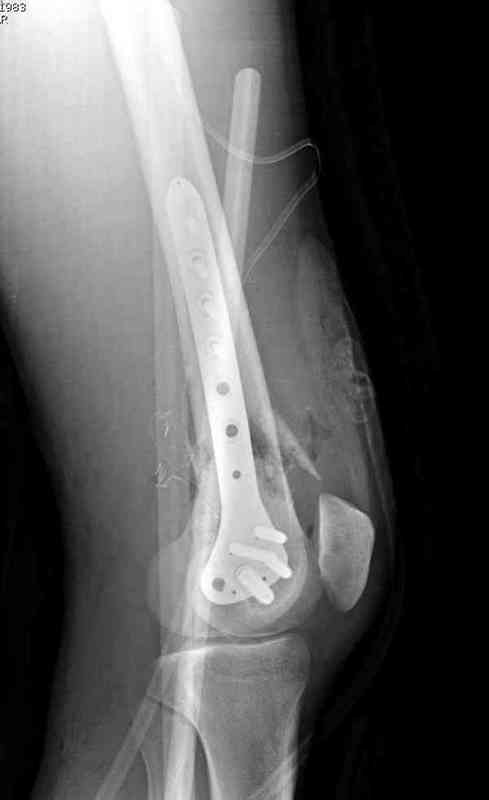

Мне кажется здесь нужна стабильная фиксация пластиной LSP DF или LSP мыщелковй пластиной для дистальной части бедренной кости, выполнить декортикацию,и с целью стимуляции остеогенеза использовать аутокость или chronOS блок

тактика стандартная при атрофических ложных суставах-lcp+костная пластика

атрофический лложный сустав-костная пластика, короткий дистальный отломок,о\пороз,нижняя конечность-lcp

If not and patient is otherwise well: locking distal femoral plate is my first choice.

This is not all that old - only two years. My choice would be to open the fracture site, freshen the ends, get as near an anatomical reduction as possible and use the locking compression plate system for fixation.

I have a similair case who had non -union after supracondylar nail, which broke at the fracture site. I had to take the nail out and then fixed it with LISS_DF (locking plate) I did use the bone graft. fracture healed with 3 months.

Next, anatomic alignment [not necessarily anatomic reduction] and lots of compression. I would use a locking plate with non locking screws proximally to allow that extra compression watching to be sure not to create excessive valgus. I would not worry about length. Bone graft as needed.

My view is that if it is hyper- or normotrophic nonunion, or partial healing i would proceed to gradual correction with ex-fix, then

conversion to a nail (my personal preference would be antegrade nailing though of course retrograde is suitable). In case of atrophic nonunion and loose mobility - site opening + grafting, fixation by a plate with angular stablity.